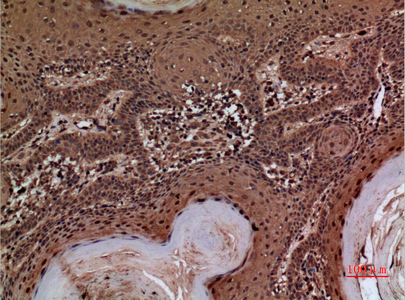

产品名称AACT Rabbit Polyclonal Antibody

推荐应用WB,IHC-P,IF-P,IF-F,IF-ICC,ELISA

免疫原The antiserum was produced against synthesized peptide derived from the Internal region of human SERPINA3. AA range:251-300

特异性AACT Polyclonal Antibody detects endogenous levels of AACT protein.

稀释度WB 1:500-1:2000, IHC-P 1:100-1:300, ELISA 1:20000, IF-P/IF-F/IF-ICC 1:50-200

背景介绍The protein encoded by this gene is a plasma protease inhibitor and member of the serine protease inhibitor class. Polymorphisms in this protein appear to be tissue specific and influence protease targeting. Variations in this protein's sequence have been implicated in Alzheimer's disease, and deficiency of this protein has been associated with liver disease. Mutations have been identified in patients with Parkinson disease and chronic obstructive pulmonary disease. [provided by RefSeq, Jul 2008],

组织表达Plasma. Synthesized in the liver. Like the related alpha-1-antitrypsin, its concentration increases in the acute phase of inflammation or infection. Found in the amyloid plaques from the hippocampus of Alzheimer disease brains.